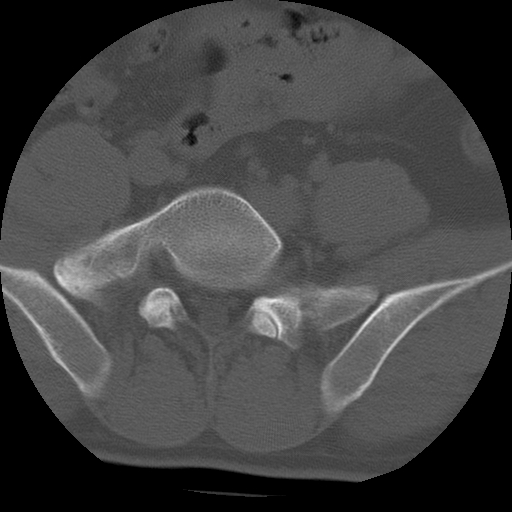

标题: CT24390:男,23岁,腰痛就诊。 [打印本页]

标题: CT24390:男,23岁,腰痛就诊。

男,23岁,腰痛就诊。

腰5右侧横突肥大伴假关节形成.

支持!图像少,再往下扫骶髂关节面,椎小关节毛糙,青年男性需排除as,实验室查b27。

腰5右侧横突肥大伴假关节形成

腰5右侧横突肥大伴假关节形成!支持!

l5右侧横突肥大伴假关节形成。

腰椎骶化或骶椎腰化常见。